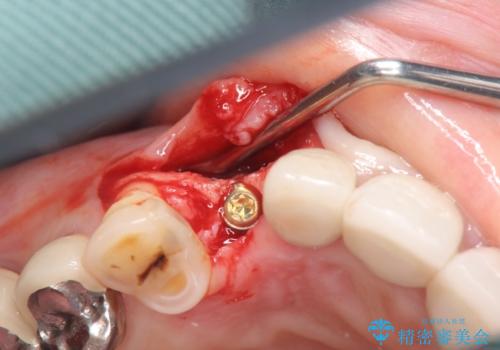

クラウン下に再発した深い虫歯 インプラントによる機能回復

- 定期検診で通院されていたところ、20年前に他院で治療した前歯のセラミック歯の下に深い虫歯が再発していることがわかりました。

ブリッジや歯の挺出を行い保存する提案も行いましたが、短期間の定期的な通院が難しくインプラントによる少ない回数での治療を希望されました。

- 45万円(ストローマンインプラント・骨造成・チタンカスタムアバットメント・ジルコニアクラウン)費用は治療当時の料金となります